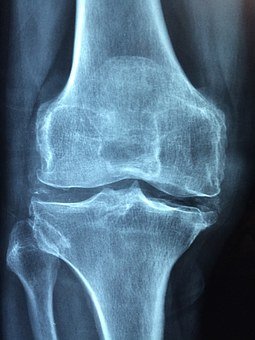

Osteoartritis merupakan jenis artritis yang paling umum menyerang dengkul. Ini merupakan proses degeneratif ketika tulang rawan pada persendian berangsur-angsur hilang. Karena itu, penyakit ini kerap terjadi pada orang tua. Osteoartritis juga dapat terjadi karena tekanan berlebih pada sendi, baik karena cedera maupun kelebihan berat badan.

Jenis artritis lainnya adalah artritis reumatoid, yaitu yang memengaruhi dengkul dan menyebabkan sendi meradang. Selanjutnya, kondisi ini menyebabkan tulang rawan pada dengkul hancur. Biasanya, artritis reumatoid terjadi pada orang-orang dengan usia muda.